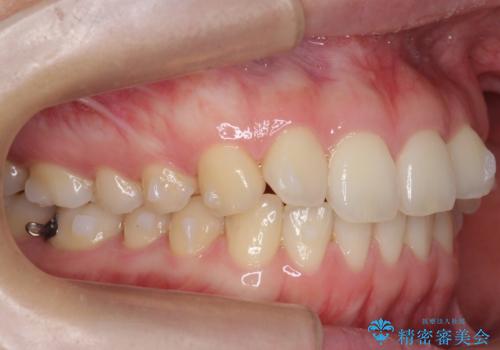

下の前歯が1本短い インビザラインと部分矯正の組み合わせ

- 前歯のガタつきと、下の前歯が一本短いことを主訴に来院。

インビザラインのマウスピースではめる装置で歯を引っ張り出すことは難しいと説明し、下の前歯だけワイヤー部分矯正を行ってからインビザライン矯正で仕上げをしました。